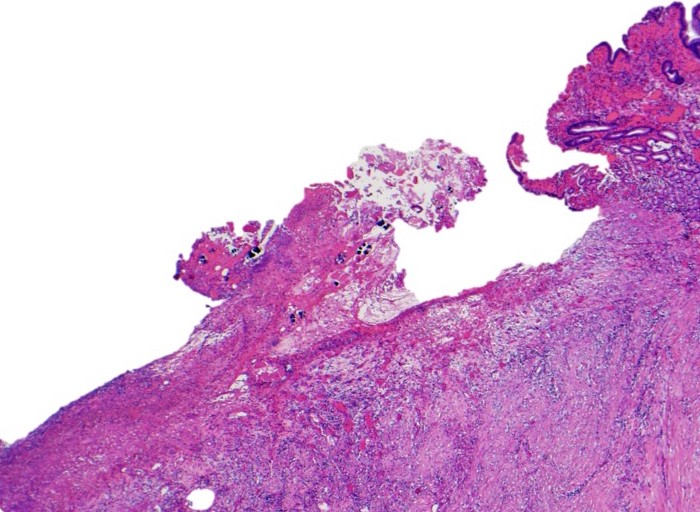

The entire ulcer was submitted for microscopic examination. No malignancy or H. Pylori identified. However, multiple bacterial cocci were noted at the ulcer bed. They are basophilic-stained and cuboid-shaped bacteria that arranged in tetrad packets, consistent with Sarcina ventriculi.

Sarcina ventriculi is anaerobic gram-positive coccus that grows in an acidic environment. It is typically diagnosed with a hematoxylin-eosin stain and, if needed, with a Gram special stain. It was first described by Goodsir in 1842 as a human pathogen. The pathogenic status of Sarcina in human is still unclear. However, association of Sarcina with a patient with gastric perforation, emphysematous gastritis, and peritonitis as well as occurring in the background of gastric adenocarcinomas has been reported. It can normally be found in the soil and air, where it can survive for years by forming spores at alkaline pH. It ferments Carbohydrate as an energy source. Sarcina species, whose natural habitat is the soil, is probably ingested with soil particles present in the food. Various reports in veterinary literature have implicated the Sarcina species in the development of gastric dilatation and death in livestock, cats and horses.

Differential diagnoses for S ventriculi are Sarcina maxima and Staphylococcus species. The most helpful feature in light microscopy to differentiate S ventriculi from S maxima is the thick extracellular layer present on the outer surface.